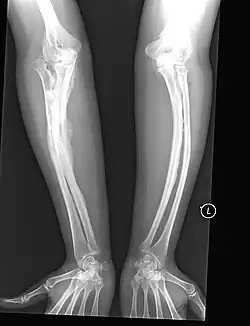

Da das Kollagen vom Typ I rund 90 % der Knochenmatrix ausmacht, ist das Hauptmerkmal der OI eine abnorm hohe Knochenbrüchigkeit. Das Synonym Glasknochen beschreibt sehr bildhaft sowohl die mechanischen Eigenschaften des wie Glas leicht zerbrechlichen Knochens als auch das Erscheinungsbild der Knochen auf Röntgenaufnahmen. Da bei der OI nur ungenügend schattengebende Knochensubstanz eingelagert ist, erhöht sich die Strahlentransparenz bei der Röntgenaufnahme, so dass der Knochen oftmals als milchglasähnliche, verwaschene Struktur dargestellt wird.

OI Typ V

Betroffene dieses Typs neigen zum seltenen Phänomen des sogenannten hyperplastischen Kallus (Callus luxurians), einer spontan überschießenden Kallusbildung ohne eine hierfür übliche Fraktur mit anschließender Verknöcherung. Durch Einlagerung von Calciumsalzen in die bindegewebigen Strukturen (Syndesmosen) zwischen den beiden Unterarmknochen Elle und Speiche sowie den Unterschenkelknochen Schien- und Wadenbein (Calcifizierung der Membranae interosseae antebrachii et cruris) ist die Ein- und Auswärtsdrehung (Pronation/Supination) des Unterarms bzw. des Unterschenkels der Betroffenen erheblich blockiert, was zur klinischen Differentialdiagnose hilfreich ist, sofern die Bewegungseinschränkungen nicht auf Deformierungen der entsprechenden Knochen oder Gelenke beruhen.